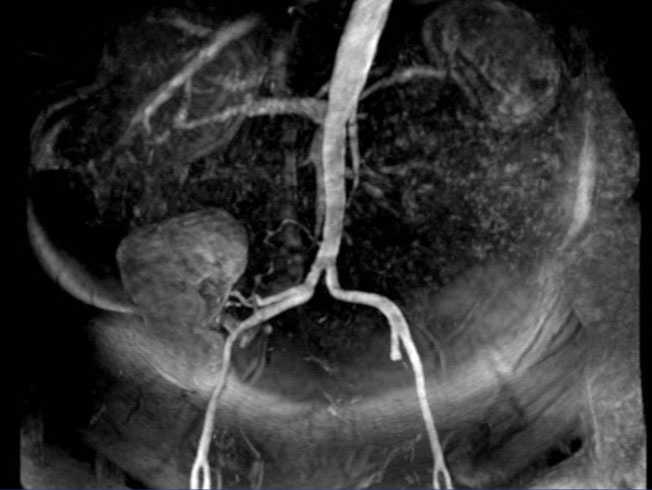

Imaging studies showed normal chest X-ray and renal ultrasound with right kidney with no structural abnormalities, except for the presence of two simple cysts in the upper pole and it was not possible to visualize the left kidney. Subsequently, renal artery CT angiography was performed and we observed almost complete stenosis of the right renal artery, 1.3cm long, at a distance of approximately 2cm from its outlet, with an 8mm aneurysm subsequent to stenosis and the presence of smaller aneurysmal dilatation. There was also left renal atrophy (Figure 1). This finding was confirmed by renal arteriography.

Figure 1. CT angiogram of renal arteries